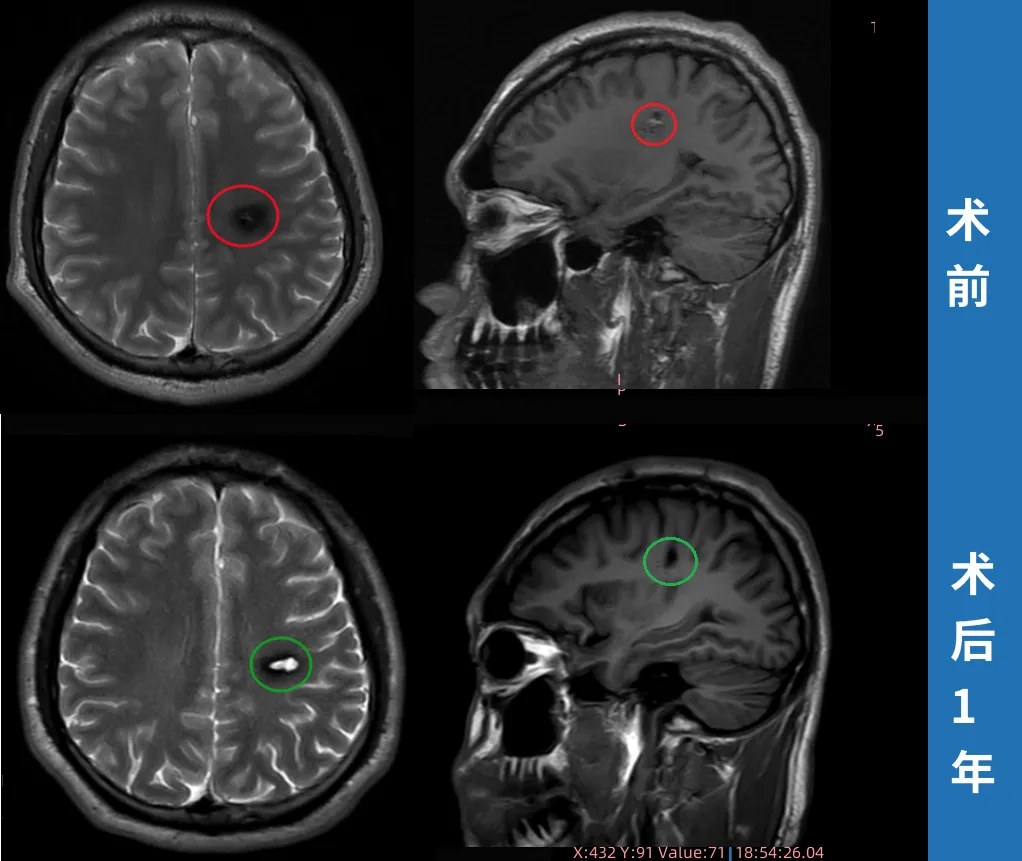

23岁男性•半卵圆中心海绵状血管瘤术后两周出院

简要病史:右手无力,写不了字,23岁的斌斌就医检查左半卵圆中心海绵状血管瘤,住院治疗一周,期间右腿、右脚无力,走路不利索,医院给予保守治疗后出院。斌斌父母一直苦苦寻求能为年轻的孩子安全手术的主刀医生。当他们看到了巴教授来华示范手术消息,于是奔赴苏州寻求教授为孩子主刀手术。

治疗过程:在苏州大学附属第四医院,巴教授已经顺利为斌斌顺利完成手术,全切左半卵圆中心海绵状血管瘤。

术后情况:术后一周,已经可以自行下床活动,术后的右手麻木等症状有所缓解,术后两周多顺利出院,现在早已恢复正常生活重回大学校园。